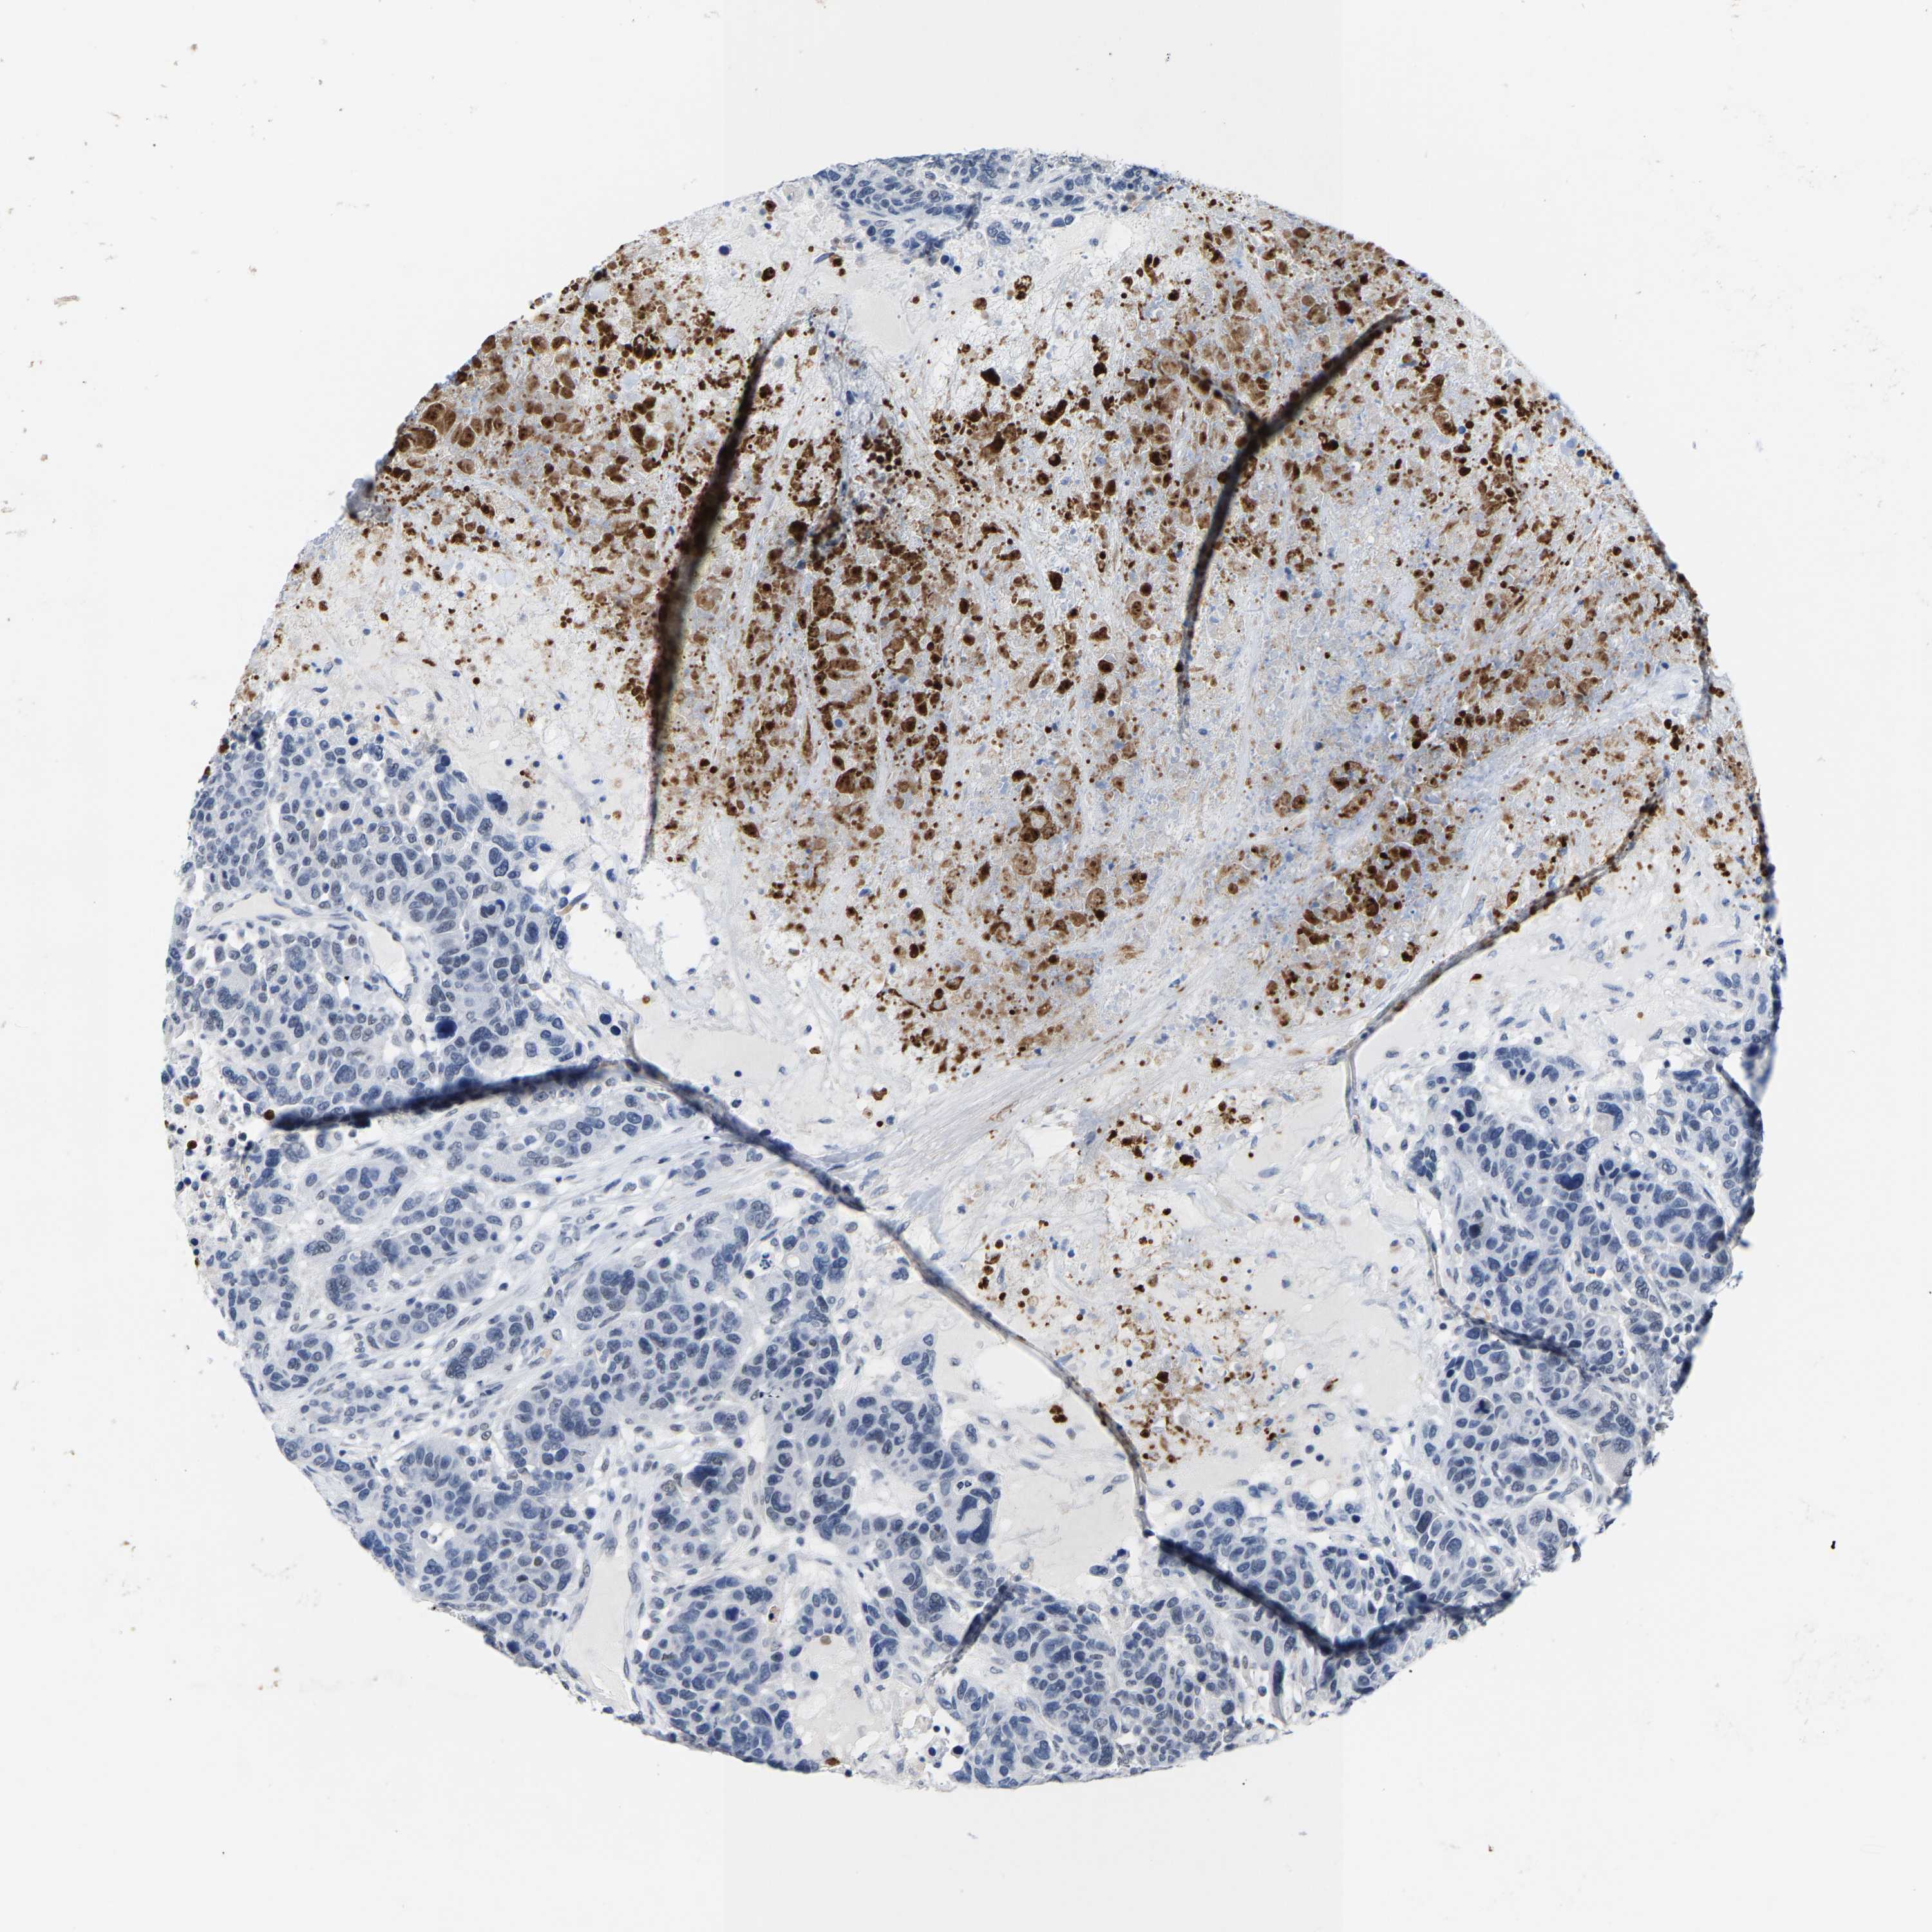

BRCA TCGA BRCA VALIDATION PROTEIN EXPRESSION